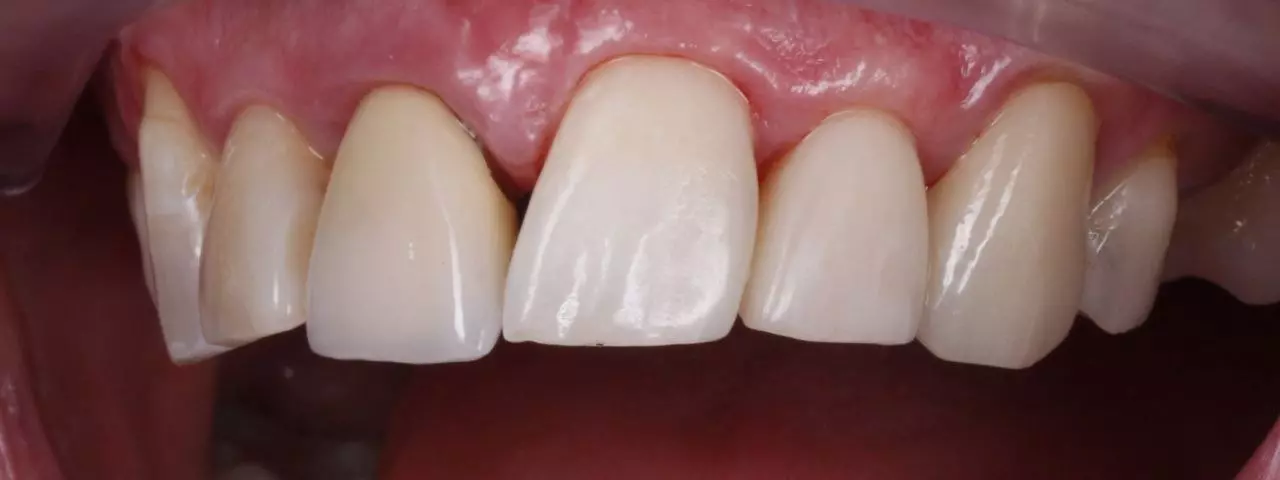

Художня реставрація

Художня реставрація 13.12.11.21.22.